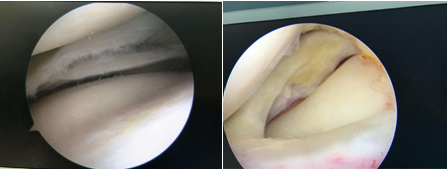

3.半月板损伤

老年患者半月板出现退变,日常活动,如上下楼梯,爬山,跳广场舞等也会引起损伤。半月板损伤会有明显的膝部撕裂感,随即关节疼痛,活动受限,走路跛行。膝关节表现出交锁、卡压、胀痛感,并且在关节活动时有弹响,甩腿有时可缓解症状。

如果是单纯滑膜增厚,可以服用中成药制剂,或者通过中医辨证施治,有时效果也很好。如果是滑膜炎晚期,滑膜增厚严重影响膝关节活动,就得使用关节镜将增厚的滑膜做适当切除,清除病变组织。如果是髌骨软化,软骨退变性损伤,可以向关节腔内注入一些起到润滑作用的药物,如玻璃酸钠等,可以起到增加润滑、缓解疼痛的作用,但不能根除,需要隔一段时间就注射一次。如果是关节内游离体、半月板损伤、韧带损伤,倘若疼痛剧烈,用药效果不明显,可以选用关节镜技术进行检查并治疗。

关节镜下膝关节清理术,临床证明关节镜下关节清理术治疗膝关节骨性关节炎,是一种微创的集关节腔内疾病诊断、治疗功能评价于一体的近代关节外科的一项重要诊疗技术。不仅完全可以达到及优于切开手术的清理效果,还具有创伤小,术后关节功能恢复快,第二天即可下床活动,患者痛苦小,并发症小而轻,必要时可重复治疗等优势。可有效缓解症状,改善功能,提高中老年患者的生活质量,延缓病程的发展。在关节镜下进行软骨刨削成形去除游离体,切除变性滑膜皱襞,切除破裂的半月板,从而消除了妨碍关节活动的机械性因素。解除关节内绞索因素和功能紊乱,去除关节内不稳定骨刺,则进一步解除了远期关节进一步退变的因素,刨除增生发炎的滑膜及大量盐水冲洗关节腔,可以将关节内磨损碎屑和炎性因子冲出关节腔,减轻炎性反应。在一定压力下充盈关节腔,不仅保证手术顺利进行,也起到松解关节的作用。